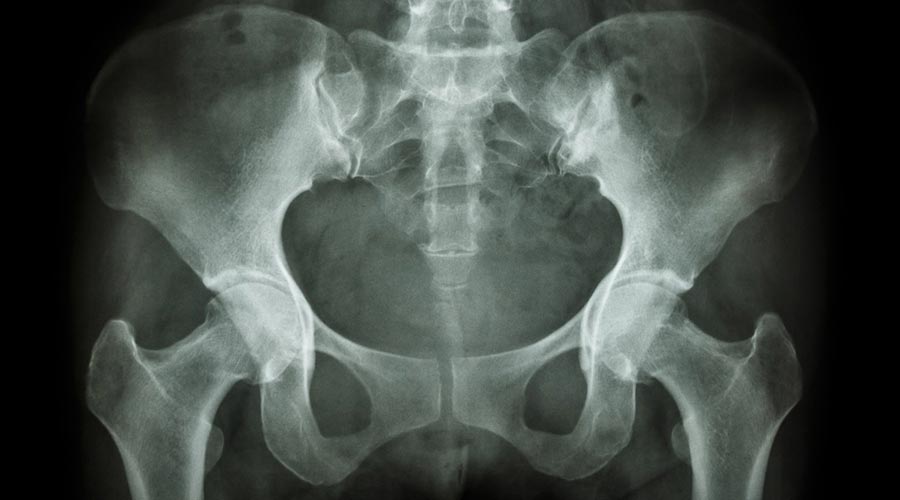

Złamania w obrębie miednicy można podzielić na złamania z przerwaniem ciągłości obręczy kończyny dolnej oraz bez przerwania tej ciągłości. Złamania